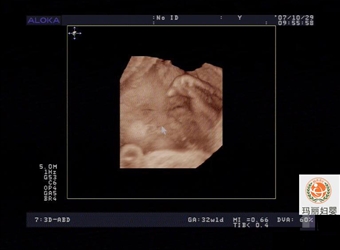

四维超声技术采用的是4D超声图像加上时间的维度参数。这项革命性的技术能够实时的获取4维图像,超越了传统超声的限制。作为一套完整的超声检查系统,主要运用…

胎儿是怎样形成的你知道吗?胎儿发育过程图其实是一个复杂的过程,育儿网本文将为大家介绍胎儿早期发育过程及B超(图),让大家更加了解胎儿的形成原因。其实…

妈妈们胎儿发育过程b超图你看过吗?在这十月怀胎期间,每一个月胎儿的变化都很大。育网小编收集到了各月胎儿发育过程图男女胎儿b超发育全过程高清图(从怀孕第…